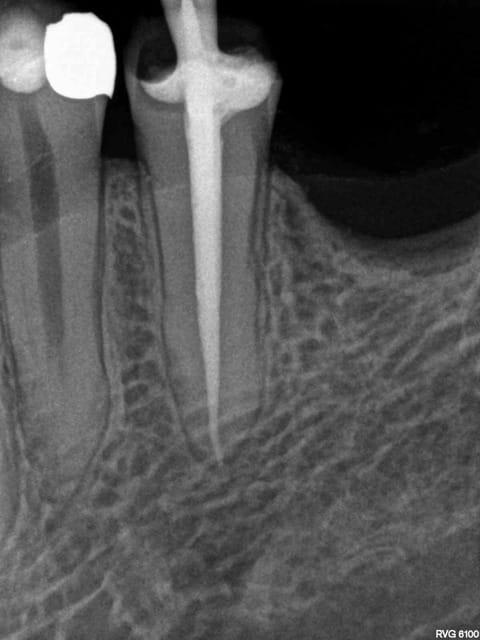

Oui -)))) postes un peu des radios de tes endos micro métrées pour voir.

La radio cone en place était un peu plus sexy. Mais ca ce sont les aléas du système B. Pour 80 boules je ne me fais pas chier à tout reprendre. ( canaux mésiaux en y tu noteras)